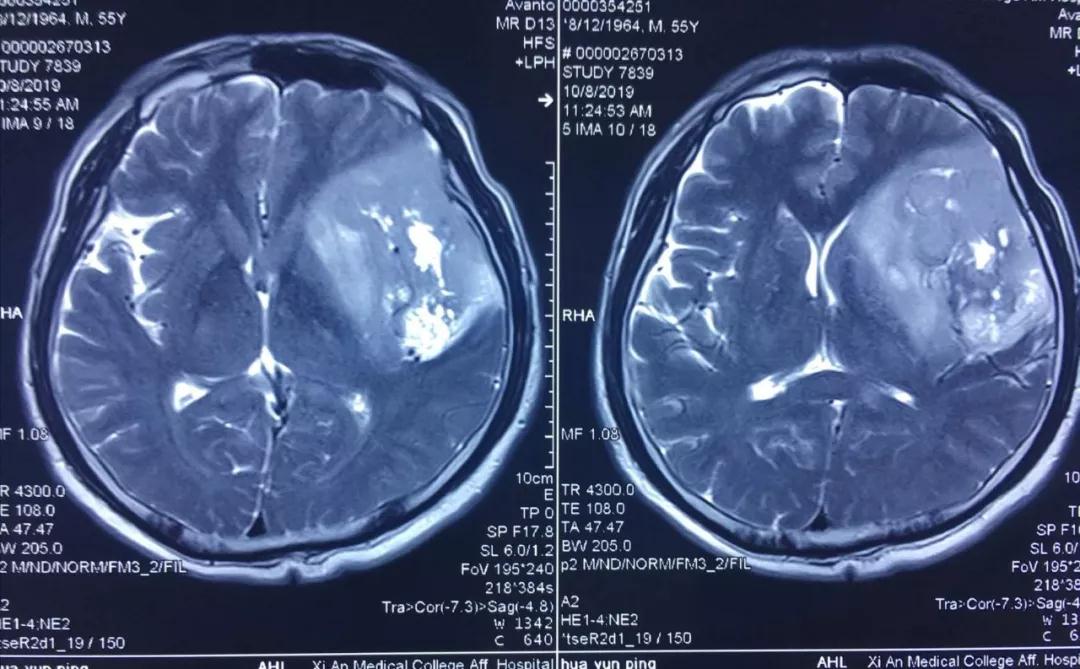

患者李某,今年55歲,因近年出現(xiàn)間歇性面部抽搐,一直未給予重視,近來發(fā)作頻繁,經(jīng)朋友建議在外院行頭顱核磁檢查,發(fā)現(xiàn)顱內(nèi)巨大占位性病變,病變位于左側(cè)額、顳和深部腦島葉,達(dá)8.5?5.5?3cm,且侵犯語言功能區(qū),顱內(nèi)占位效應(yīng)明顯,中線偏移1cm,且腫瘤已經(jīng)瀕臨腦疝邊緣,如不及時(shí)進(jìn)行手術(shù)干預(yù),隨時(shí)有腦疝可能,危及患者生命。

經(jīng)多方了解后,在朋友的推薦下,患者慕名來到西安國際醫(yī)學(xué)中心找到了腦科醫(yī)院高國棟院長,高院長帶領(lǐng)以賀世明主任為首的神經(jīng)外科團(tuán)隊(duì),對(duì)患者的病情及治療方案等進(jìn)行討論,憑借多年的臨床經(jīng)驗(yàn),結(jié)合患者影像結(jié)果判斷為顱內(nèi)膠質(zhì)瘤,并建議盡快實(shí)施手術(shù)切除。